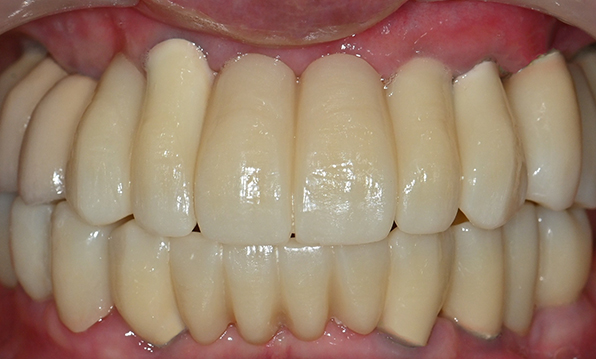

전체 임플란트

위 아래 치아가 정확하게 맞아야하는 고난이도 임플란트

임상 경험이 많은 숙련된 전문의의 섬세한 기술력이 중요합니다.

치료기간 : 2021.04.12~2021.09.15